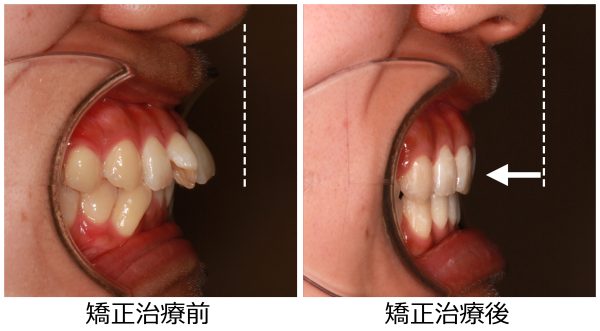

27歳 女性 「 ねじれ歯、出っ歯を治したい 」 ( 翼状捻転 )

上の前歯が ねじれて 傾斜しているため

前歯だけが 目立ってしまいます。

前歯のねじれを鳥の翼に例えて、翼状捻転と呼ばれる状態です

前歯も傾斜しているため ”出っ歯” 感も強いです。

捻じれと 出っ歯を治したいとの事で矯正治療を開始しました。

ねじれと ”出っ歯”を治したいとの事で

上下左右の 抜歯を行い 前歯を後方に移動させました。

抜歯により、前歯の捻じれと 出っ歯感が解消しました。

前歯は大きく下がりました。

前歯のねじれは改善し、大きく下がりました

前歯が大きく下がったことで、口もとの 印象が 大きく変わり

口もともスッキリと変化しました。

27歳 女性 叢生を伴う 上顎前突症 治療期間15か月 唇側矯正装置(ホワイトワイヤー)を使用した上下顎第一小臼歯抜歯治療 参考治療費 約65万円 (精密検査から終了まで) 矯正治療に伴う副作用の歯肉退縮、知覚過敏、失活、歯根吸収などは認められませんでした。